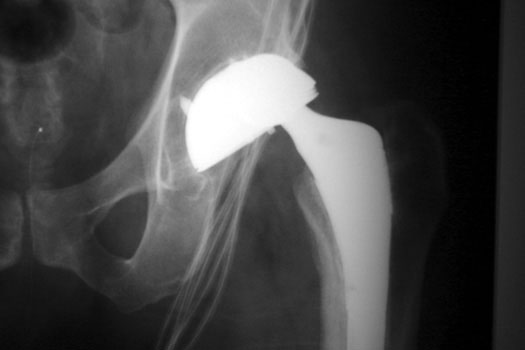

OSTEOLYSIS—ABOUT ACETABULAR COMPONENT GRUEN ZONE II, WITH PATHOLOGIC FRACTURE